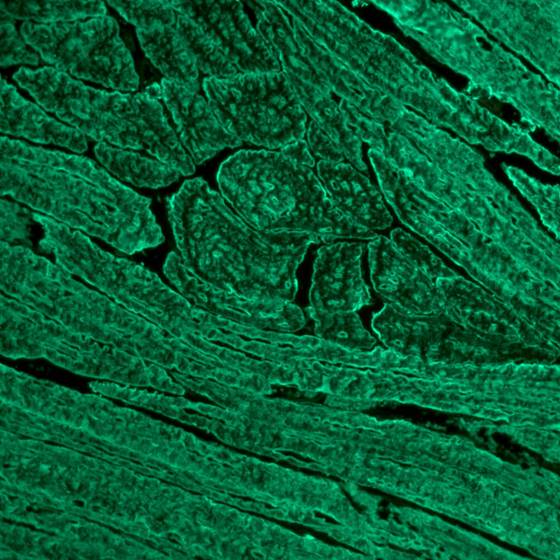

Objektträger beschichtet mit Skelettmuskulatur-Gewebeschnitten (Ratte) zum Nachweis von Antikörpern gegen Skelettmuskulatur aus Serum oder Plasma mittels Immunfluoreszenz.